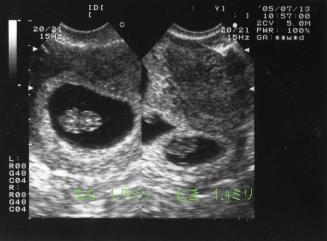

7月13日8W3D